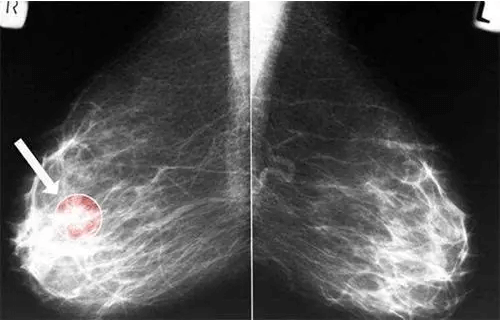

1、乳房出现肿块:肿块常常是无痛的,不规则形状、单个,肿块为实性,比较硬,活动度比较差。乳腺癌的好发部位是乳房的外上象限位置 2、乳房局部皮肤出现改变:乳房的皮肤出现“酒窝征”的变化,就需要提高警惕了。 3.乳头改变:当乳腺癌的病灶侵袭到乳头或是乳晕下区域时候,乳腺的纤维组织和导管系统就可能会以为肿瘤的侵犯出现缩短的症状。然后牵拉乳头,就会使得乳头偏向肿瘤的那一侧。 如果进一步的发展,可能会出现乳头扁平、凹陷、回缩甚至是完全的缩到乳晕下面,看不到乳头。4、乳头溢液:当乳腺导管上皮出现增生、炎症、出血或是坏死、肿瘤病变的时候就可能会出现乳头溢液。 乳头溢液可能会是无色的但也可能是有颜色的如乳白色、淡黄色,重一点的颜色可能会是棕色。呈现出水样、浆液性、脓性或是血样。5、疼痛:会有隐痛或者是刺痛的症状出现。……[详情]